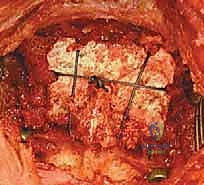

الخطوة 2: الشق الجراحي والتعرض

يقوم الدكتور هطيف بعمل شق جراحي دقيق في منتصف الجزء الخلفي من الرقبة. يتم إبعاد العضلات برفق للوصول إلى العظام الخلفية للفقرتين C1 و C2. هنا، تبرز أهمية الجراحة الميكروسكوبية لتقليل النزيف والحفاظ على الأنسجة المحيطة.

الخطوة 3: تحديد المعالم التشريحية وحماية الشريان الفقري

هذه هي الخطوة الأكثر حساسية. باستخدام أدوات دقيقة جداً وتحت تكبير الميكروسكوب، يتم تحديد الحواف العظمية للفقرة C1 والفقرة C2. يتم تحديد مسار العصب العنقي الثاني (C2 nerve root) وإبعاده بلطف. كما يتم تحديد المنطقة المجاورة للشريان الفقري لضمان بقاء المسامير بعيدة عنه تماماً.

الخطوة 6: تركيب القضبان واستعادة المحاذاة (Reduction)

بعد وضع المسامير الأربعة بنجاح، يتم تقييم وضعية الفقرات. إذا كانت C1 منزلقة للأمام، يتم استخدام أدوات خاصة لسحبها للخلف واستعادة المحاذاة الطبيعية مع C2 (عملية تُسمى Reduction). بمجرد تحقيق الوضعية المثالية، يتم قص قضيبين من التيتانيوم بالطول المناسب وتثبيتهما بقوة في رؤوس المسامير. هذا يخلق "سقالة" معدنية صلبة تمنع أي حركة بين الفقرتين.